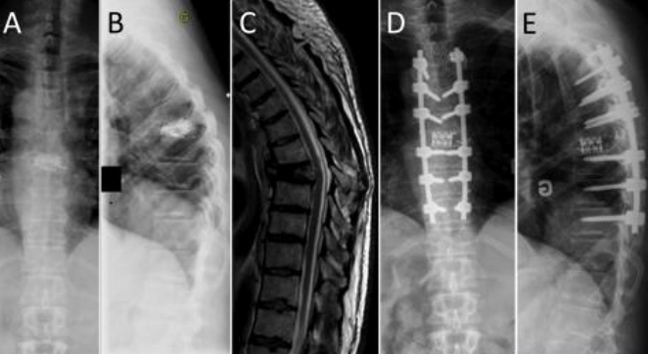

Τα τραυματικά κατάγματα της θωρακικής μοίρας της σπονδυλικής στήλης, είτε κατά τη διάρκεια τροχαίου ατυχήματος, είτε από πτώση από ύψος, είναι πολύ σοβαρή κατάσταση, γιατί μπορεί να προκαλέσουν παραπληγία από συμπίεση του νωτιαίου σωλήνα.

Τα κατάγματα της θωρακικής μοίρας της σπονδυλικής στήλης από ατύχημα συνήθως χρειάζονται χειρουργική αντιμετώπιση (σπονδυλοδεσία).

Σε περίπτωση παραπληγίας (που συνοδεύει το κάταγμα) δηλαδή αδυναμία κίνησης στα πόδια και αδυναμία ούρησης, η εγχείρηση (σπονδυλοδεσία) δεν εξασφαλίζει την αποκατάσταση της λειτουργίας των ποδιών. Χρησιμεύει μόνο για την στήριξη του σπασμένου σπονδύλου.